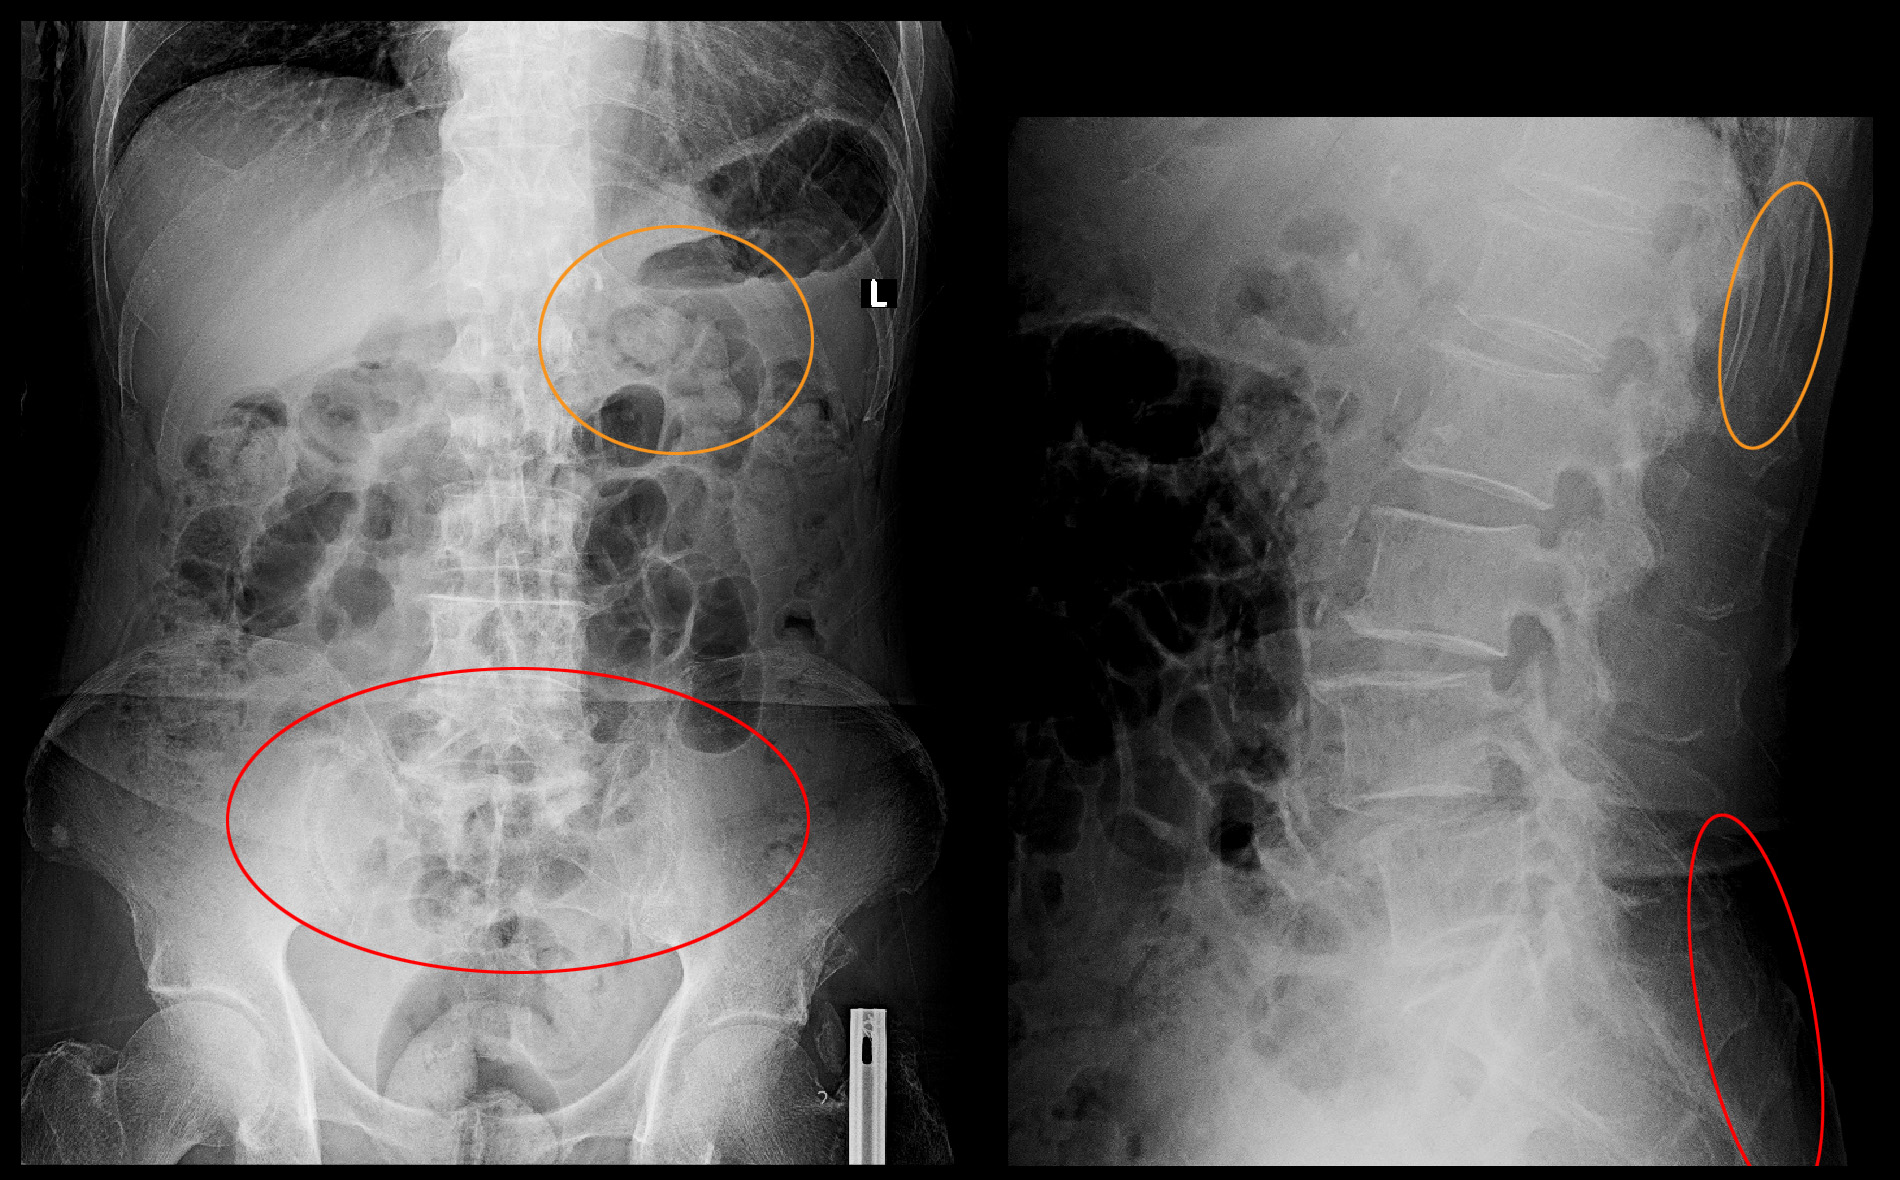

82才男 Xp2.jpg

オレンジ丸の領域が第12胸椎圧迫骨折受傷時の腰痛で、4月15日に相談された時の腰痛は赤丸領域となります。